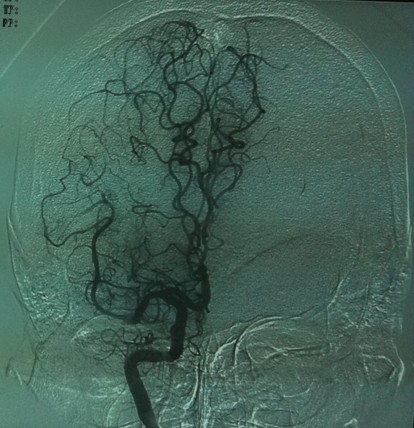

造影见右侧颈内动脉成残端

在微导丝引导下通过微导管进行接触性动脉溶栓

35mg r-tPa溶栓后见右侧颈内动脉开通,大脑前及大脑中动脉显影良好